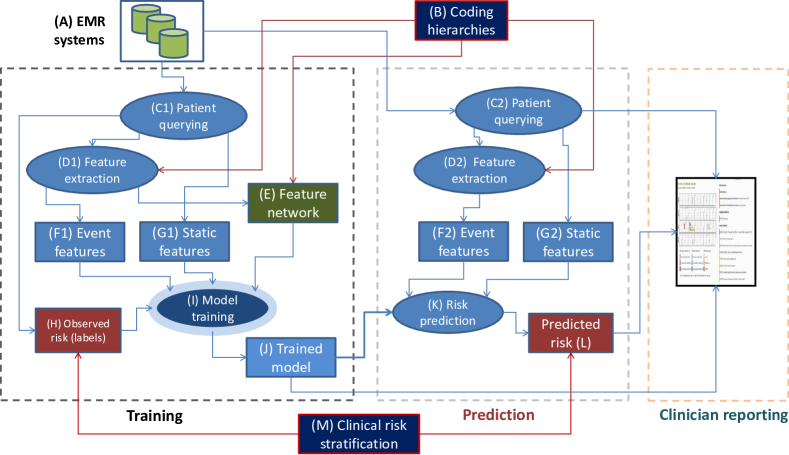

The framework is built on the patient-specific data queried from the relational EMR systems (denoted as A in Fig. 1). Patient data contains time-stamped events (such as emergency visits, diagnoses, and hospitalizations) and static information (such as gender, spoken language and occupation). For each patient, there are one or several evaluation points from which future risk will be predicted (Fig. 2). Often clinical risk assessments, hospital admissions or discharges serve as natural evaluation points as the outcomes will be tracked and acted upon.

The feature extraction process (D1,D2) generates event features (F1,F2) over multiple periods of times prior to an evaluation point (Section 4.2). The extraction process makes use of pre-defined coding hierarchies (B) such as the international disease coding scheme ICD-10111http://apps.who.int/classifications/icd10 and the Australian intervention coding scheme ACHI222http://www.aihw.gov.au/procedures-data-cubes. In the training phase, the process also generates a feature network (E) which encodes the temporal and semantic relations between features. For example, if depressive episodes were observed twice in the history, then the two features representing them are temporally linked. On the other hand, if another mental disorder is also observed, then the two disorders as semantically linked. The feature network will be used later on to improve the model stability.

The feature extraction process effectively flattens the structured EMRs into vectors, however temporal and hierarchical information is partially preserved. This process typically produces a large pool of features, and thus a feature selection capacity is needed. This is realized through model training (I) with lasso-style regularization [61]. More formally, let be the training data set, where denotes the feature vector of data instance and the discrete ordinal output. We aim to learn a sparse, linear risk model parameterized by the weight vector . The lasso-regularized loss function is as follows:

where is a convex loss function of training instance and is the regularization parameter. To accommodate ordered risk classes, we employ several probabilistic ordinal classifiers what make different assumptions about the stratification process (Section 5). The loss function is therefore the negative log-likelihood of the outcomes given the features .

The method proposed in this paper is based on the intuition that strong prior knowledge would lead to less variation due to sampling noise since prior knowledge is independent of sampling procedures. In clinical domains, prior knowledge could be realized by using feature networks, exploiting the relations between diseases and disease progression over time. In Fig. 1, the feature network (E) links related features and ensures that similar features have similar weights. This can be nicely formulated in a Bayesian regularization fashion as the feature network serves as a backbone for a precision matrix of the multivariate Gaussian prior distribution. Section 6 presents the network regularization in more details.